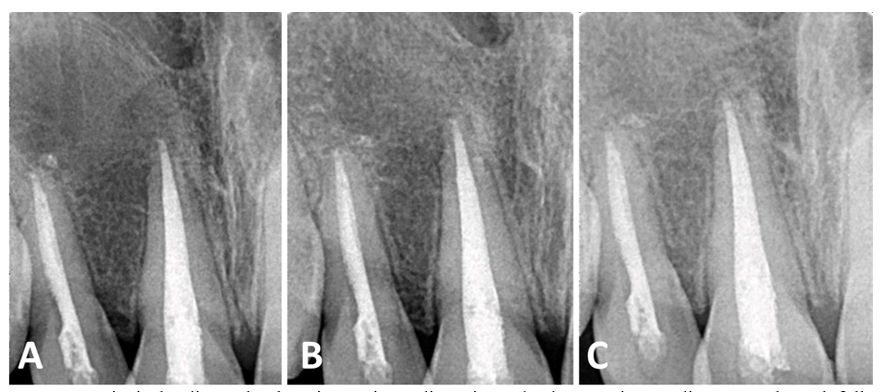

A 13‐year‐old male child had a chief complaint of a severely mesially displaced upper right lateral incisor (#12), which made his parents seek orthodontic treatment (Figure 1). The child was referred from the Department of Orthodontics to the Department of Endodontics for periapical surgery before the orthodontic treatment. The patient had no significant medical problems, and the upper right central incisor # 11 had a Class IV composite restoration. A cold vitality test with an ice stick showed no response in central #11 and lateral incisors # 12.

Figure 1 Pre-operative clinical photos showing lateral view. (A) and occlusal view (B) of a tilted lateral right incisor (tooth #12) (arrow).